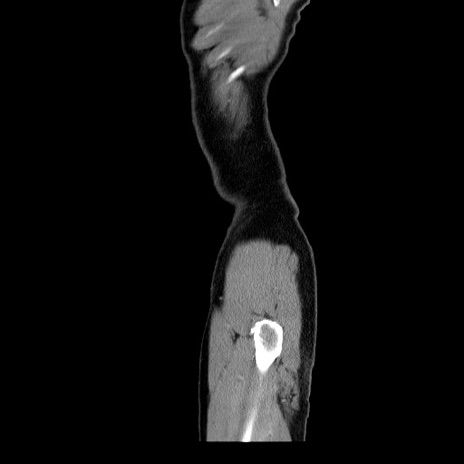

症例34(矢状断像)

【症例】60歳代 男性

【主訴】右鼠径部膨隆

【現病歴】1年程前より右鼠径部膨隆あり。自己にて還納可能だったため放置していた。3時間前より右鼠径部の脱出を認め、還納困難となり受診。

【身体所見】右鼠径部に小児頭大の膨隆あり。弾性硬であり、用手還納は困難。左鼠径部にも膨隆を認める。脱出はなし。